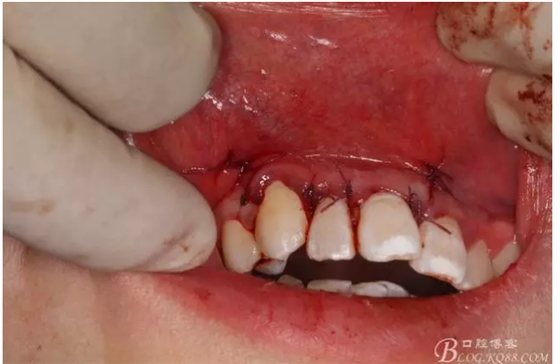

圖14.縫合水平切口

圖15.縫合垂直切口

圖16.縫合完畢,一周拆線。